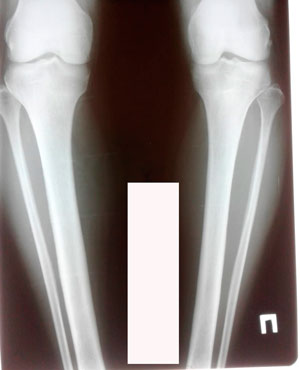

Исходник 38 лет.

Дата операции - 16.03.2020

image-17-03-20-05-45-3.jpg

image-17-03-20-05-45-6.jpg